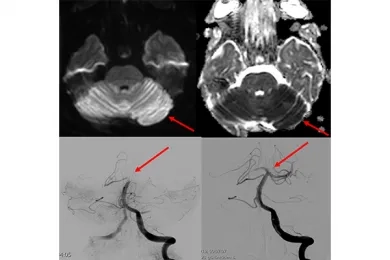

If stroke symptoms have not gone away for more than 6 hours, and if a blockage is detected in one of the main arteries in the brain, interventional radiology comes into play at this point. In the angiography unit, small pipes (catheters) are placed to the clot in the occluded artery in the brain by entering through the groin or the wrist, and the clot is mechanically removed and the blood flow in the occluded artery is restored to normal. When we look at the literature, it has been shown that mechanical removal of the clot, even in periods up to 6-24 hours after the emergence of stroke symptoms, allows the patient to continue his/her life independently or less dependently.

If the acute stroke is treated early, it becomes possible for patients to continue their lives without any disability or addiction. Some of our patients who come with sudden paralysis and speech disorders start to move their arms and legs after the clot is removed while they are still on the angiogram table, and their speech improves, they ask us questions, answer our questions, and return to work within a few days. These situations and moments we encounter in treatment are really pleasing.